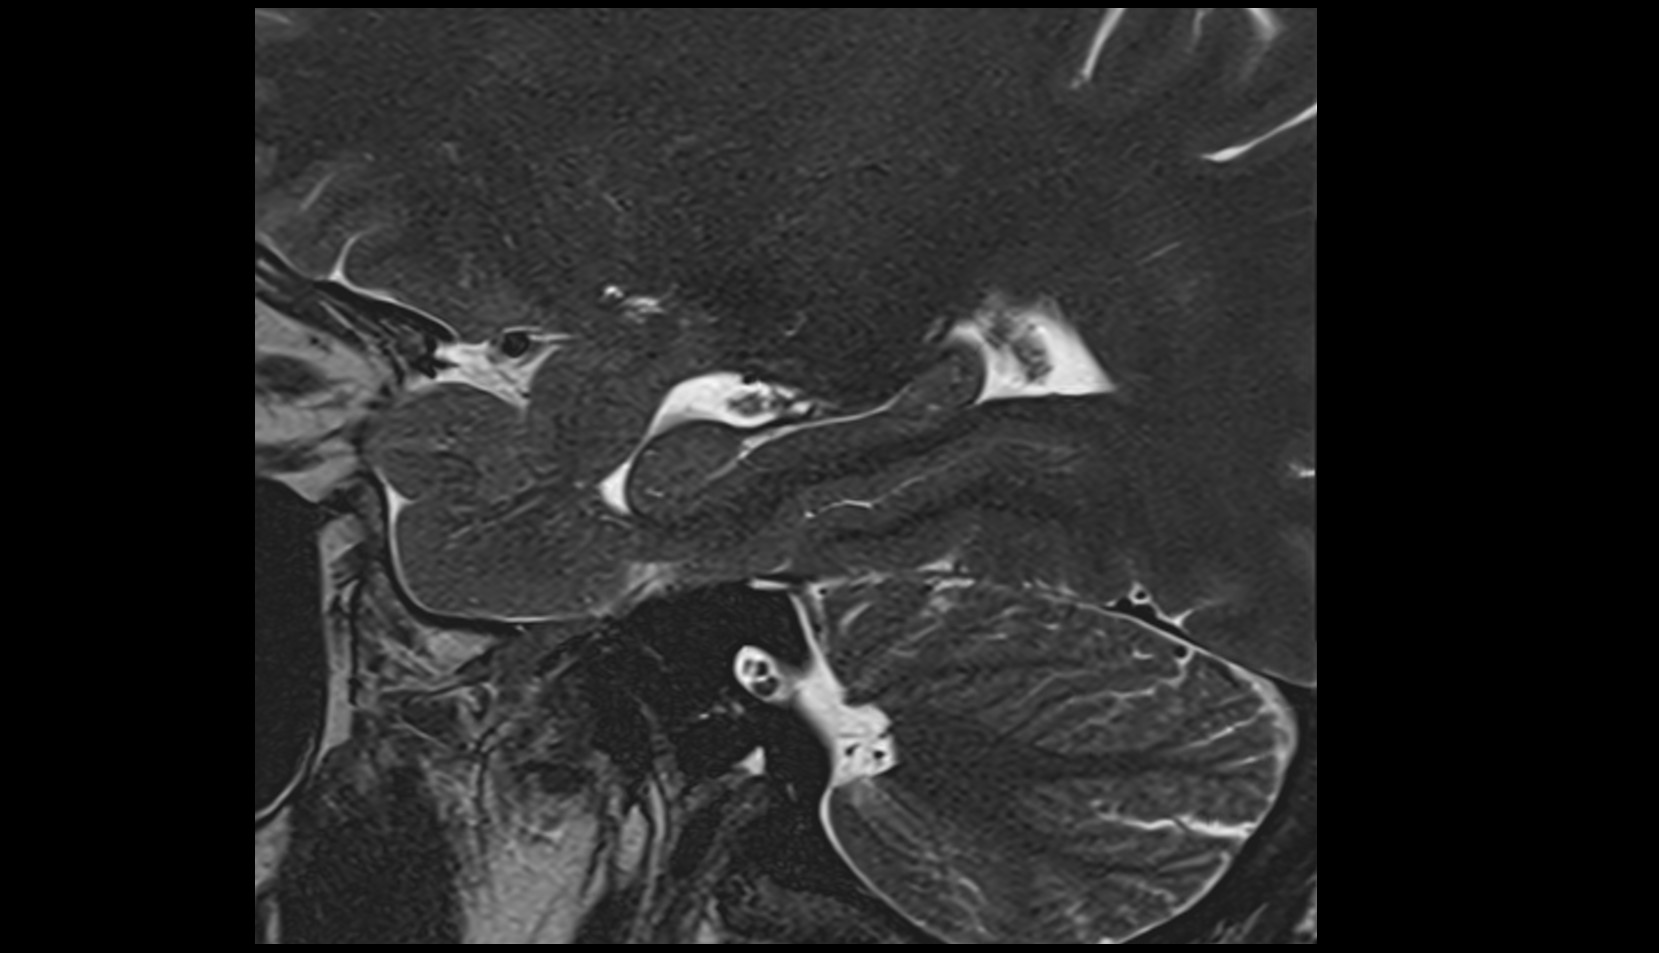

- Temporomandibular joint

- Mandibular condyle

- Mandibular fossa

- Articular disc of temporomandibular joint

- Articular eminence